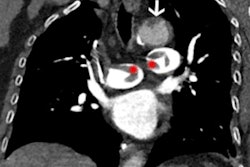

A large thrombus is seen in the left atrial appendage (LAA) behind the device on (A and B) the coronal PET and PET/cardiac MRI images as well as (C and D) the axial PET and PET/cardiac MRI images. (E and F) 2D balanced steady state free precession cines stacks in the coronal and axial planes have been combined into a single 3D dataset and fused with the 3D PET data. In these multimodality images, the PET and MR data are both displayed in 3D, creating a volumetric depiction of the heart and the thrombus/Cu-64 FBP8 containing LAA. Volume-rendered images in the oblique coronal and axial planes confirm the presence of thrombus in the LAA. (A to F) The thrombus produced by the closure device is contained within the LAA, and no evidence of thrombus is seen elsewhere in the heart or thorax. Image courtesy of JACC: Cardiovascular Imaging.SUVmax values in the LAA were significantly higher in patients with clots in the LAA than those without. An SUVmax threshold of 2.6 yielded a sensitivity of 100% and specificity of 84%, as evaluated by a radiologist with 15 years of experience, the researchers wrote.